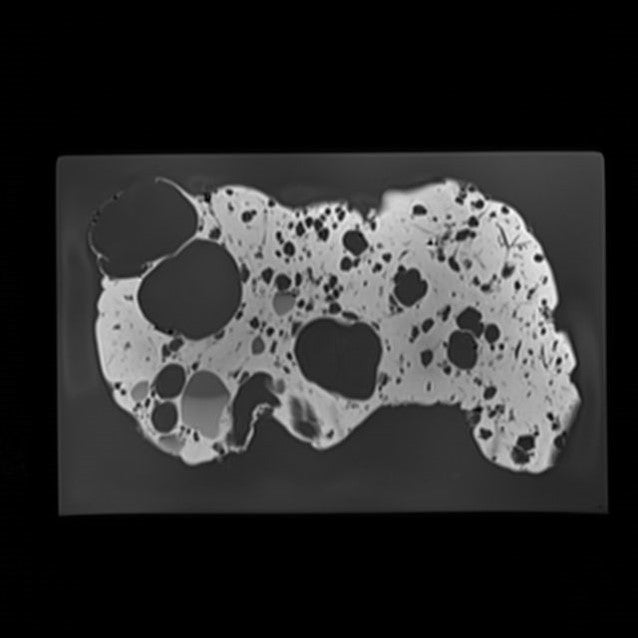

Liver - Congenital Polycystic Disease